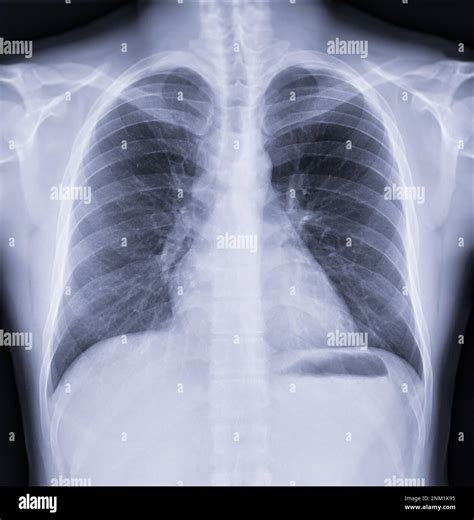

**Normal Chest X Ray: The Quiet Diagnostic Tool Shaping Healthcare & Wellness Conversations in America** Curious about what a normal chest X ray really means—and why so many people are asking about it? This imaging test is a cornerstone of preventive health, serving as a quiet yet powerful window into lung and heart health. While often discussed behind medical scenes, growing public awareness is turning the normal chest X ray into a topic of everyday health dialogue across the U.S. Whether for routine checkups, travel health, or unexplained symptoms, understanding how this scan works—and when it matters—helps people feel more informed and empowered. ### Why normal chest x ray Is Gaining Attention in the US Beyond routine medical procedures, the normal chest X ray has become a focal point amid rising awareness of respiratory health and preventive care. With increased focus on early diagnosis and lifestyle-informed wellness, the test’s role extends beyond diagnosis to guiding everyday health decisions. Its accessibility, low cost, and non-invasive nature make it a go-to tool for both clinicians and proactive individuals navigating minor symptoms or pre-travel screenings. Social conversations and digital health platforms now normalize checking in on fundamental health markers—making the chest X ray a foundation in holistic health strategies. ### How normal chest x ray Actually Works